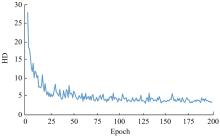

针对脑皮层下组织部分结构(如纹状体)在医学影像中目标小、对比度低,图像分割难度大,在自动医学诊断中应用比较困难的问题,本文基于深度学习的方法提出了一种医学图像分割网络,在磁共振成像中分割组成纹状体的苍白球、尾状核、壳核3部分。本文提出的网络模型具有捕获全局和局部特征的能力,并建立了全局与局部信息的相关性,在深度不退化的同时有效融合不同尺度的深层语义特征和浅层细节特征,实现对纹状体的精确分割。模型在公开的脑部数据集上进行了验证,并与其他先进的方法进行对比,结果表明本文的戴斯相似系数、平均交并比、95%豪斯多夫距离分别为94.26%、90.94%、3.82,均优于其他几种方法,达到了先进水平,这表明本文模型可以提高对纹状体的分割精度,为相关疾病的研究提供依据。